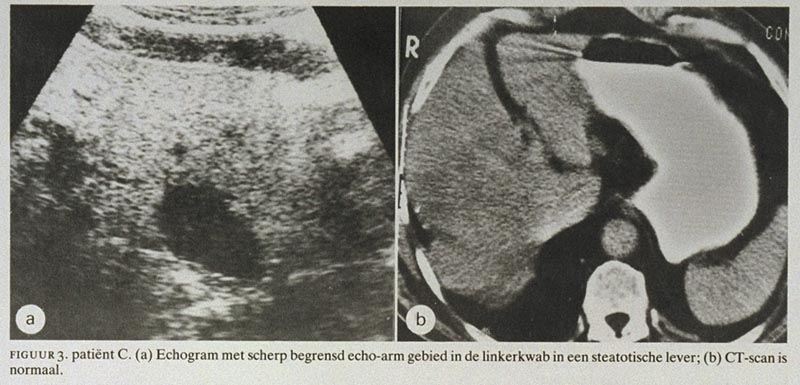

Patiënt C, een 75-jarige man die in het verleden nefrectomie had ondergaan als gevolg van een Grawitz-tumor, werd vanwege aspecifieke bovenbuikklachten echografisch onderzocht. In een steatotische lever werden drie scherp omschreven echo-arme focale afwijkingen gevonden, waarvan één in de linkerkwab en twee in de rechterkwab, die deden denken aan metastasen (figuur 3a). Er waren geen leverfunctiestoornissen en een CT-scan was normaal (figuur 3b). Een dunne-naaldbiopt dat onder echogeleide uit de afwijking in de linker leverkwab genomen werd, liet normale levercellen zien, zodat de diagnose FNS werd gesteld. Follow-up-onderzoek na 3 maanden toonde echografisch een onveranderd beeld van de lever aan en klinisch waren er ook dan geen aanwijzingen voor metastasen.